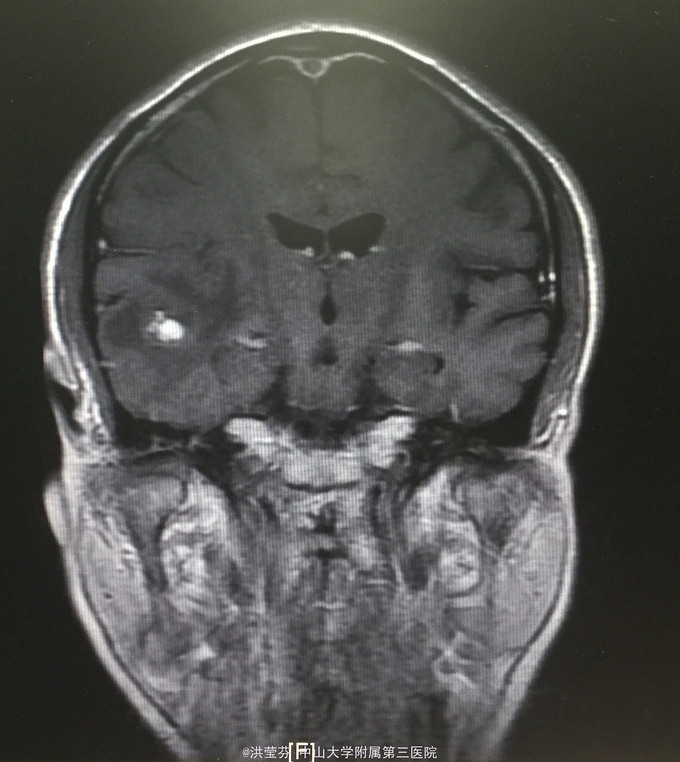

查体:KPS 60分,BSA 1.83m2,T 38.5℃,全身浅表淋巴结未触及明显肿大,胸壁可见浅表静脉曲张,呼吸急促,左下肺、右中下肺呼吸音明显减弱,其余肺野呼吸音促,可闻及少许实性啰音,心率110bpm,律齐,腹软,全腹无压痛、反跳痛,未扪及明显包块,肝脾肋下未触及,移动性浊音(——),肠鸣音正常,4次/分,双下肢无凹陷性水肿。 辅助检查:血常规无特殊,生化转氨酶稍升高,低钠低氯,CRP 227.9mg/L,凝血四项:Fib 8.14g/L。复查胸部CT提示:1.胸腺癌并纵膈淋巴结及双肺多发转移瘤,右心房、上腔静脉受侵并癌栓形成,病变较前进展。2.双肺炎症,以右肺为著。3.双侧胸腔及心包积液。上腹部CT提示:1.下腔静脉早显并肝表面多发侧支形成,考虑右心流出道阻塞所致;腹壁静脉曲张。头颅MR提示右侧颞叶强化灶,结合病史,考虑转移瘤,伴瘤灶少量出血可能,瘤周脑水肿。